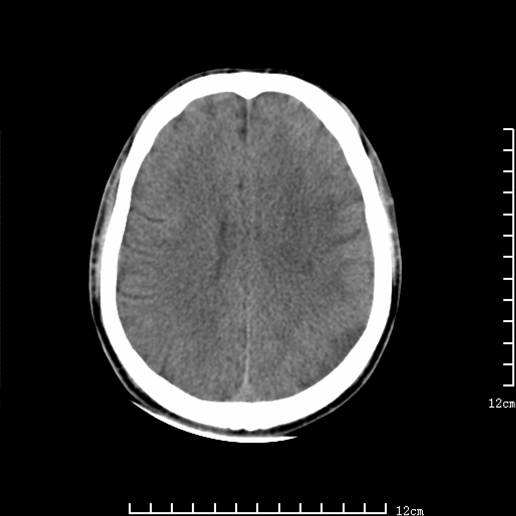

以下图像分别是3月25日凌晨及下午图像、3月27日、4月16日的ct图像。

3月25日凌晨